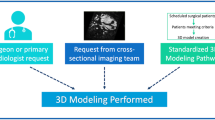

Once the five (5) patient studies were identified for modeling, DICOM data were anonymized and exported from the ultrasound device in a grayscale format with a Cartesian coordinate system, which allowed for importation of the volume into the segmentation software, Mimics v20.0 (Materialise, Leuven, Belgium). The DICOM files were uploaded to a secure remote server for transfer to collaborators at 3D Systems Healthcare for segmentation, model design, and 3D printing (JF, SA).